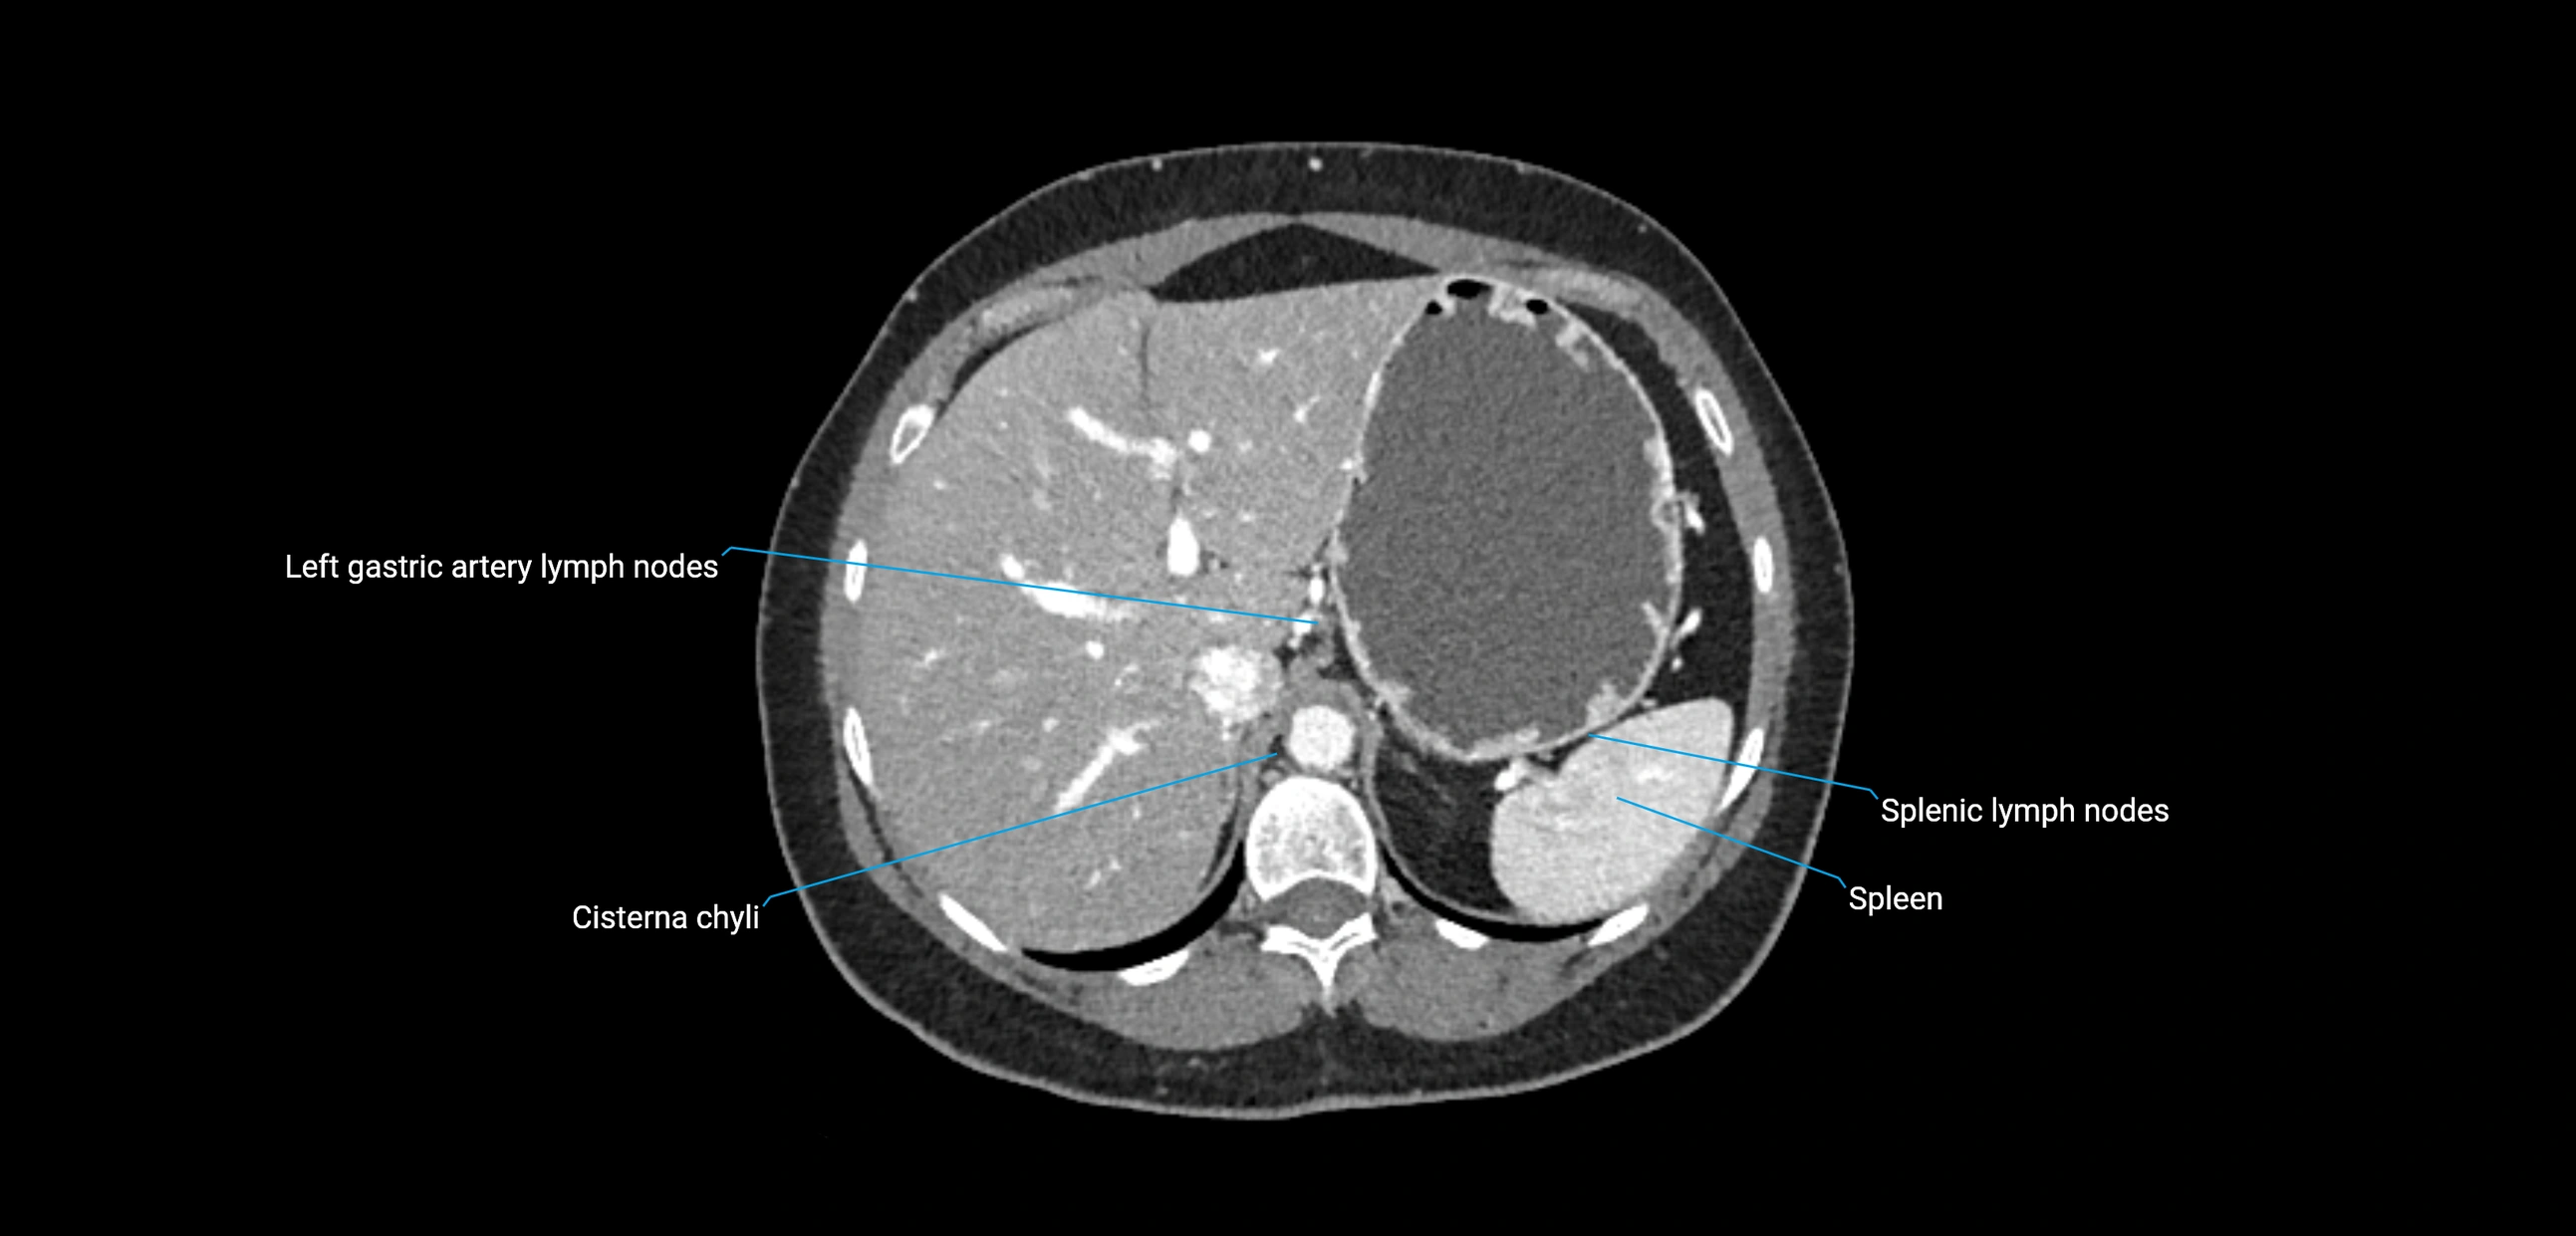

CT Appearance

CT Pre-Contrast:

• Nodes appear as soft-tissue density nodules adjacent to the aorta and IVC

CT Post-Contrast:

• Normal nodes enhance homogeneously

• Malignant nodes may show heterogeneous enhancement, central necrosis, or conglomerate formation

• Size >1 cm short axis is suspicious, though morphology and distribution are equally important